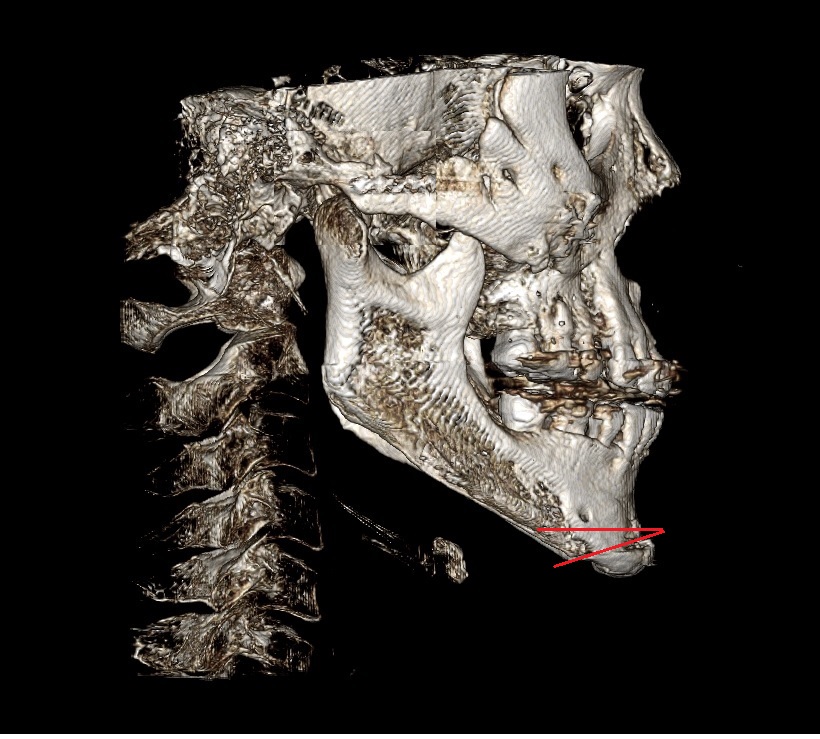

1. 원장님 말씀대로 턱끝을 다시 후방으로 이동시켜야될 목표를 가지고 수술을 계획을 세워야될거 같습니다

3. 일단 원장님이 말씀하신대로나온 주걱턱 느낌 턱끝을 뒤로 후퇴 시킬려고생각합니다 후퇴 시키는 방법ㅇ 중에 두가지를 고려하고 있습니다 일단첫번째 방법으론 기존 절골선을 이용하여 다시 절골후 후퇴 시키는 방법 아래 도완 첨부합니다 삼각형식으로 파서 절골해서 올려 부치는 방법 장단점좀 알려주세요

6. 후퇴를 시키면 원장님 저의 턱끝길이가 살짝 길이감이 있는데 이건 어떤방법으로 줄이나요?